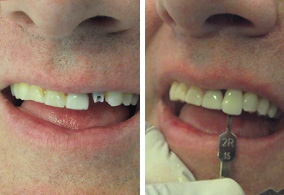

Replace teeth that have been lost with the passage of the years restoring functionality and aesthetics to your mouth.A dental implant is a cylinder shaped dental root manufactured alloplastic material (usually titanium) which is surgically implanted under the gums inside the maxillary or mandibular bone; once placed and osseointegrated, the dentist will place upon them crowns or fixed bridges that will replace the teeth lost, then the implant helps us provide retention and support a fixed or removable dental prosthesis.

This system consists of leaning into two or three and sometimes even on 4 dental implants to hold all of the prosthesis or implant a complete denture which is retained by those 4 implants. This procedure is recommended to patients who for lack of economic opportunities or for reasons of age or time, cannot be a process longer and more complex, as it would be to implement more roots and hold the denture more pillars of the implant.

The Dental implant merges with the bone of the jaw thus creating a stable support for the fake teeth, dentures, bridges and individual crowns placed upon implants will not move inside the mouth, providing comfort and safety when it comes to chewing and speaking.